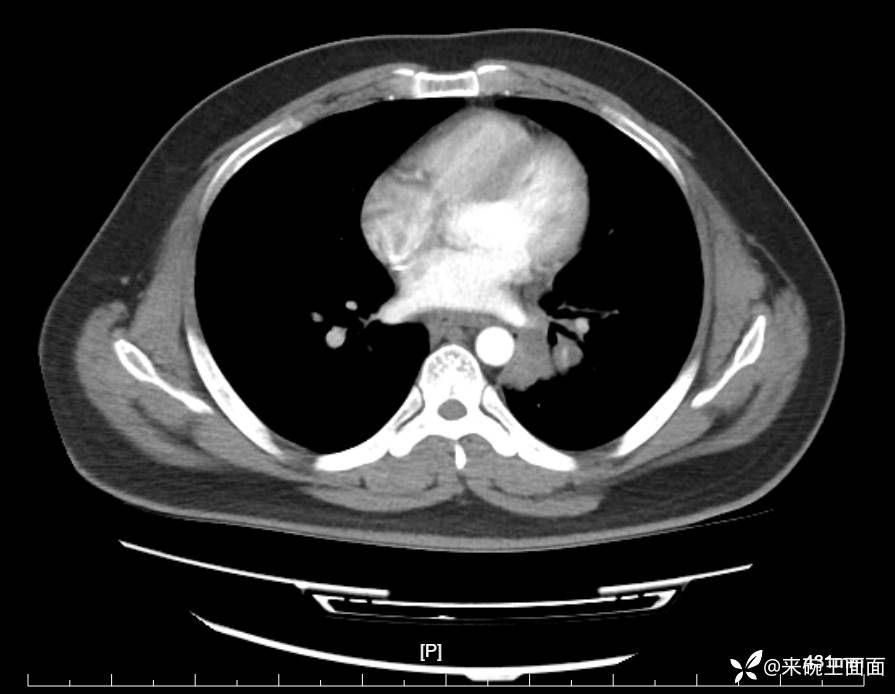

性别:男

年龄:27岁

主诉:胸闷胸痛数月余,休息后可自行缓解,无咯血症状。

个人史:数年吸烟史,具体不详。